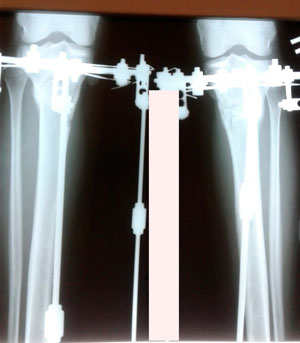

Исходник - 32 года.

Дата операции - 12.09.2019г.